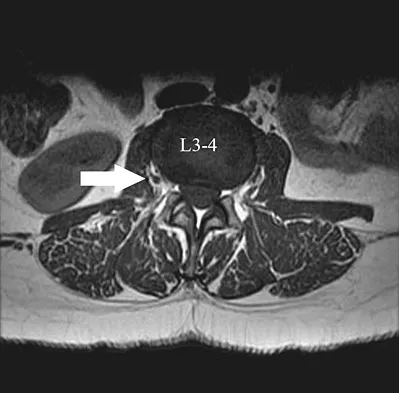

Which of the following patient factors is associated with recurrent radicular pain following lumbar diskectomy for sciatica?

Explanation